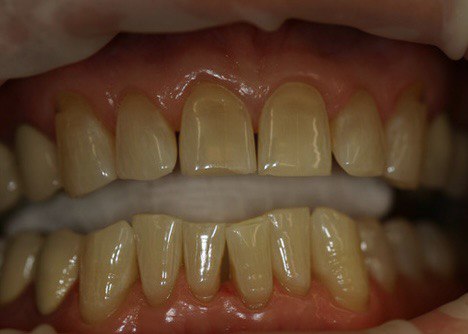

Пациент 51 года обратился с жалобой на тёмные зубы.

Проведено отбеливание зубов с применением диодного лазера.

До процедуры цвет зубов А3 по шкале VITA, после процедуры цвет зубов В1 по шкале VITA.